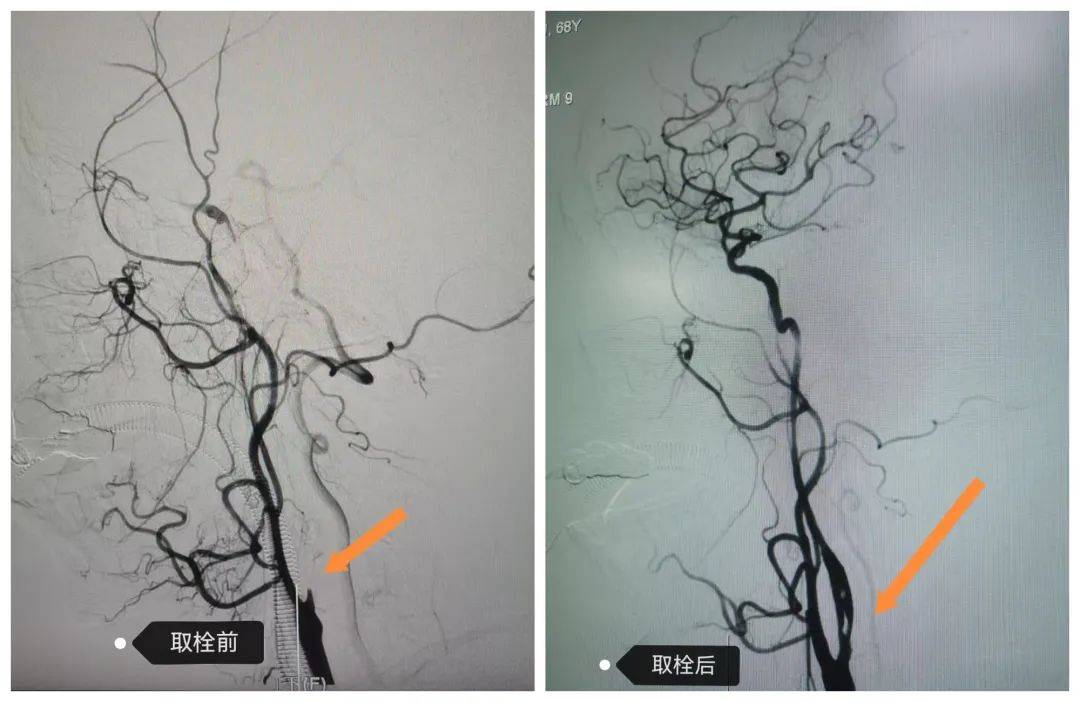

02機(jī)械取栓術(shù)綻放“遲開的花”,為大面積腦梗死患者搶時(shí)間

68歲的戶大爺突發(fā)言語不清、左側(cè)肢體無力3小時(shí)后入院,值班醫(yī)師衛(wèi)小冬通過頭顱核磁確診大面積腦梗死,且病情有進(jìn)一步惡化風(fēng)險(xiǎn)。在劉彥書主任帶領(lǐng)下,介入團(tuán)隊(duì)于入院 2 小時(shí)內(nèi)完成術(shù)前準(zhǔn)備并實(shí)施顱內(nèi)取栓術(shù)。目前患者癥狀持續(xù)改善,康復(fù)出院指日可待。